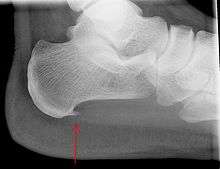

An incidental finding associated with this condition is a heel spur, a small bony calcification on the calcaneus (heel bone), which can be found in up to 50% of those with plantar fasciitis.[6] In such cases, it is the underlying plantar fasciitis that produces the heel pain, and not the spur itself.[12] The condition is responsible for the creation of the spur though the clinical significance of heel spurs in plantar fasciitis remains unclear.[11]

Imaging

Medical imaging is not routinely needed as it is expensive and does not typically change how plantar fasciitis is managed.[13] When the diagnosis is not clinically apparent, lateral view x-rays of the ankle are the recommended imaging modality to assess for other causes of heel pain such as stress fractures or bone spur development.[7]

Normally the plantar fascia has three fascicles with the central fascicle thickest at 4 mm, the lateral fascicle at 2 mm and the medial at less than a millimeter in thickness.[16] In theory, the likeliness of fasciitis increases with increasing thickness of plantar fascia at the calcaneal insertion, with thickness of more than 4.5 mm being somewhat useful on ultrasound and 4 mm on MRI.[17] Findings on imaging such as plantar aponeurosis thickening, however, may be absent in symptomatic individuals or present in asymptomatic individuals thereby limiting the utility of such observations.[12]